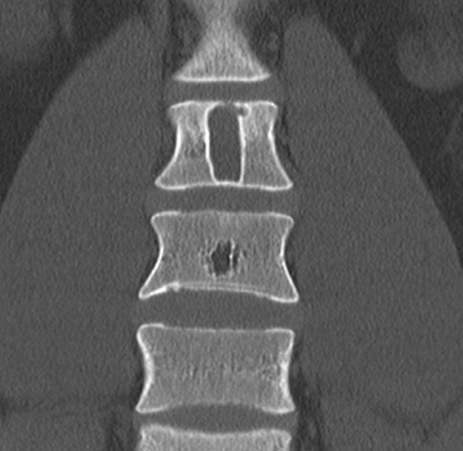

Для уточнения диагноза выполняют рентгенологическое исследование пораженного сегмента: рентгенографию бедренной кости, рентгенографию плечевой кости и т. д. На основании рентгенологической картины определяют фазу патологического процесса. В фазе остеолиза на снимке обнаруживается бесструктурное разрежение метафиза, соприкасающееся с зоной роста. В фазе отграничения на рентгенограммах видна полость с ячеистым рисунком, окруженная плотной стенкой и отделенная от зоны роста участком нормальной кости. В фазе восстановления на снимках выявляется участок уплотнения костной ткани или небольшая остаточная полость.

Различают две формы аневризмальных костных кист: центральную и эксцентрическую. В течении болезни выделяют такие же фазы, как и при солитарных кистах. Клинические проявления достигают максимума в фазе остеолиза, постепенно уменьшаются в фазе отграничения и исчезают в фазе восстановления. На рентгенограммах в фазе остеолиза выявляется бесструктурный очаг с внекостным и внутрикостным компонентом, при эксцентричных кистах внекостная часть по размеру превышает внутрикостную. Надкостница всегда сохранена. В фазе отграничения между внутрикостной зоной и здоровой костью образуется участок склероза, а внекостная зона уплотняется и уменьшается в размере. В фазе восстановления на рентгенограммах обнаруживается участок гиперостоза или остаточная полость.